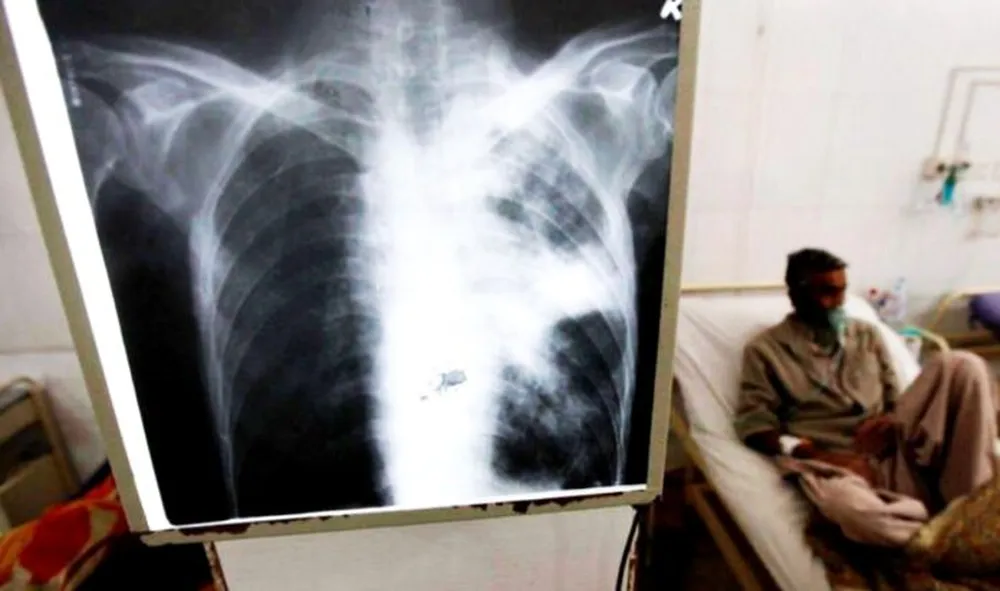

La tuberculosis – según describe el Ministerio de Salud bonaerense – es una enfermedad infectocontagiosa, causada por una microbacteria denominada Mycobacterium tuberculosis, conocida como “Bacilo de Koch” en honor a su descubridor, Roberto Koch, en el año 1882.

Se trata de una enfermedad curable, de notificación obligatoria, prevenible y de tratamiento gratuito, que afecta a los pulmones pero también puede dañar otros órganos como ganglios, cerebro y columna vertebral. Es importante el diagnóstico temprano y realizar un tratamiento completo con antibióticos sin interrupciones.